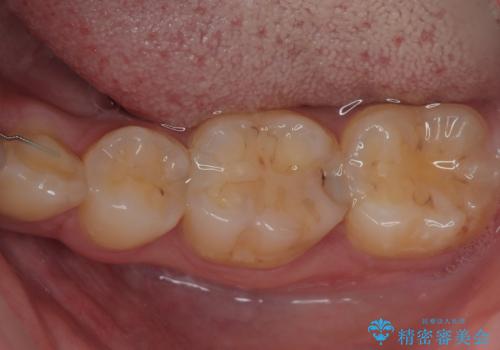

- 当院で矯正治療を終えて、左下が虫歯になっている気がするとのことで来院された患者様です。レントゲン検査の結果、コンポジットレジンによる修復箇所が複数行われており、詰め物の下に虫歯を認めました。

拡大鏡視野下でコンポジットレジン、虫歯の除去を行い、オールセラミッククラウンに適した形に整えました。